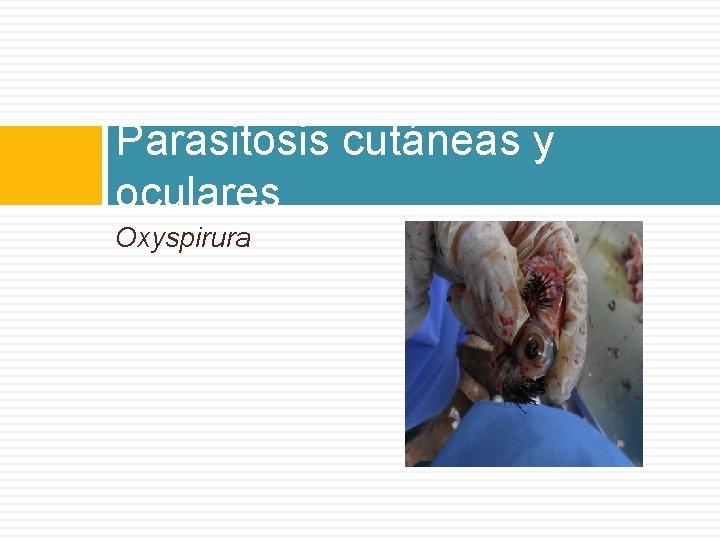

Parasitosis cutáneas y oculares Oxyspirura

Etiologia: Oxyspirura mansoni Oxyspirura parvorum Oxyspirura petrowi

Localizacion: • Membrana nictitante • Conducto nasolagrima l • Sacos conjuntivos

Diagnóstico: Heces: coprologico Observacion de los gusanos bajo membrana nictiante y saco conjuntivo.